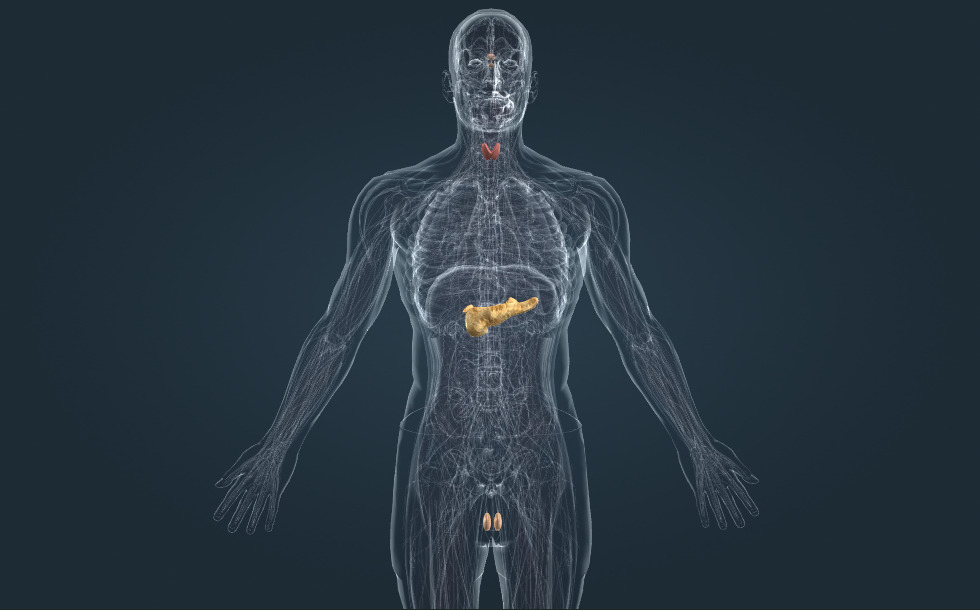

Ενδοκρινικό σύστημα

- παραθυρεοειδείς αδένες - Εκκρίνουν την παραθυρεοειδή ορμόνη (παραθορμόνη), η οποία αυξάνει τη συγκέντρωση ασβεστίου στο αίμα. Η καλσιτονίνη, που εκκρίνεται από το θυρεοειδή αδένα, έχει το αντίθετο αποτέλεσμα, μειώνει τη συγκέντρωση ασβεστίου στο αίμα.

- επινεφριδικός αδένας - Αποτελείται από φλοιό και μυελό. Ο φλοιός εκκρίνει ορμόνες που αυξάνουν το επίπεδο του νατρίου και της γλυκόζης στο αίμα. Ο μυελός παράγει την επινεφρίνη (αδρεναλίνη), η οποία είναι η ορμόνη του άγχους και παίζει σημαντικό ρόλο στην αντίδραση σε έντονο στρες.

- όρχις - Παράγει το σπερματοζωάριο και την τεστοστερόνη (ανδρική φυλετική ορμόνη), η οποία προάγει την ωρίμανση του σπερματοζωαρίου και την ανάπτυξη του ανδρικού σώματος και της τριχοφυίας.

- πάγκρεας - Εκκρίνει την ινσουλίνη, η οποία μειώνει το επίπεδο της γλυκόζης στο αίμα. Η ανεπάρκεια ινσουλίνης προκαλεί διαβήτη.

- θυρεοειδής αδένας - Εκκρίνει την ορμόνη Τ4 (τυροσίνη), η οποία αυξάνει τη βιολογική οξείδωση. Παίζει σημαντικό ρόλο στη φυσιολογική ανάπτυξη του εγκεφάλου και του σώματος. Η υπερβολική παραγωγή θυρεοειδικών ορμονών προκαλεί τη νόσο Γκρέιβς, ενώ ο υποθυρεοειδισμός προκαλεί βρογχοκήλη ή κρετινισμό (που προκαλείται από το συγγενή υποθυρεοειδισμό).

- υπόφυση - Μαζί με τον υποθάλαμο, δημιουργεί τον άξονα υποθαλάμου-υπόφυσης, το κέντρο του ορμονικού μας συστήματος.

Οι ορμόνες παράγονται από τους αδένες του ενδοκρινικού συστήματος. Η αδρεναλίνη, για παράδειγμα, εκκρίνεται από τα επινεφρίδια, η ινσουλίνη από το πάγκρεας, και η θυροξίνη από το θυρεοειδή αδένα. Το κέντρο του ενδοκρινικού συστήματος είναι ο άξονας υποθαλάμου-υπόφυσης. Ο υποθάλαμος παράγει ορμόνες που ρυθμίζουν την υπόφυση και διεγείρουν την παραγωγή των ορμονών της. Αυτές οι ορμόνες διεγείρουν άλλους ενδοκρινείς αδένες: το θυρεοειδή αδένα, τα επινεφρίδια και τους αναπαραγωγικούς αδένες. Το πάγκρεας δε ρυθμίζεται από τον άξονα υποθαλάμου-υπόφυσης.

Οι ορμόνες παράγονται από τους αδένες του ενδοκρινικού συστήματος. Η αδρεναλίνη, για παράδειγμα, εκκρίνεται από τα επινεφρίδια, η ινσουλίνη από το πάγκρεας, και η θυροξίνη από το θυρεοειδή αδένα. Το κέντρο του ενδοκρινικού συστήματος είναι ο άξονας υποθαλάμου-υπόφυσης. Ο υποθάλαμος παράγει ορμόνες που ρυθμίζουν την υπόφυση και διεγείρουν την παραγωγή των ορμονών της . Αυτές οι ορμόνες διεγείρουν άλλους ενδοκρινείς αδένες: το θυρεοειδή αδένα, τα επινεφρίδια και τους αναπαραγωγικούς αδένες. Το πάγκρεας δε ρυθμίζεται από τον άξονα υποθαλάμου-υπόφυσης.